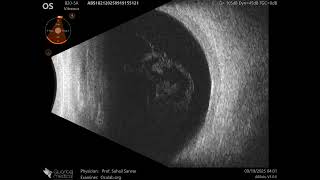

20 MHz Annular Ophthalmic Ultrasound ABSolu, Subhyaloid hemorrhage , 36660